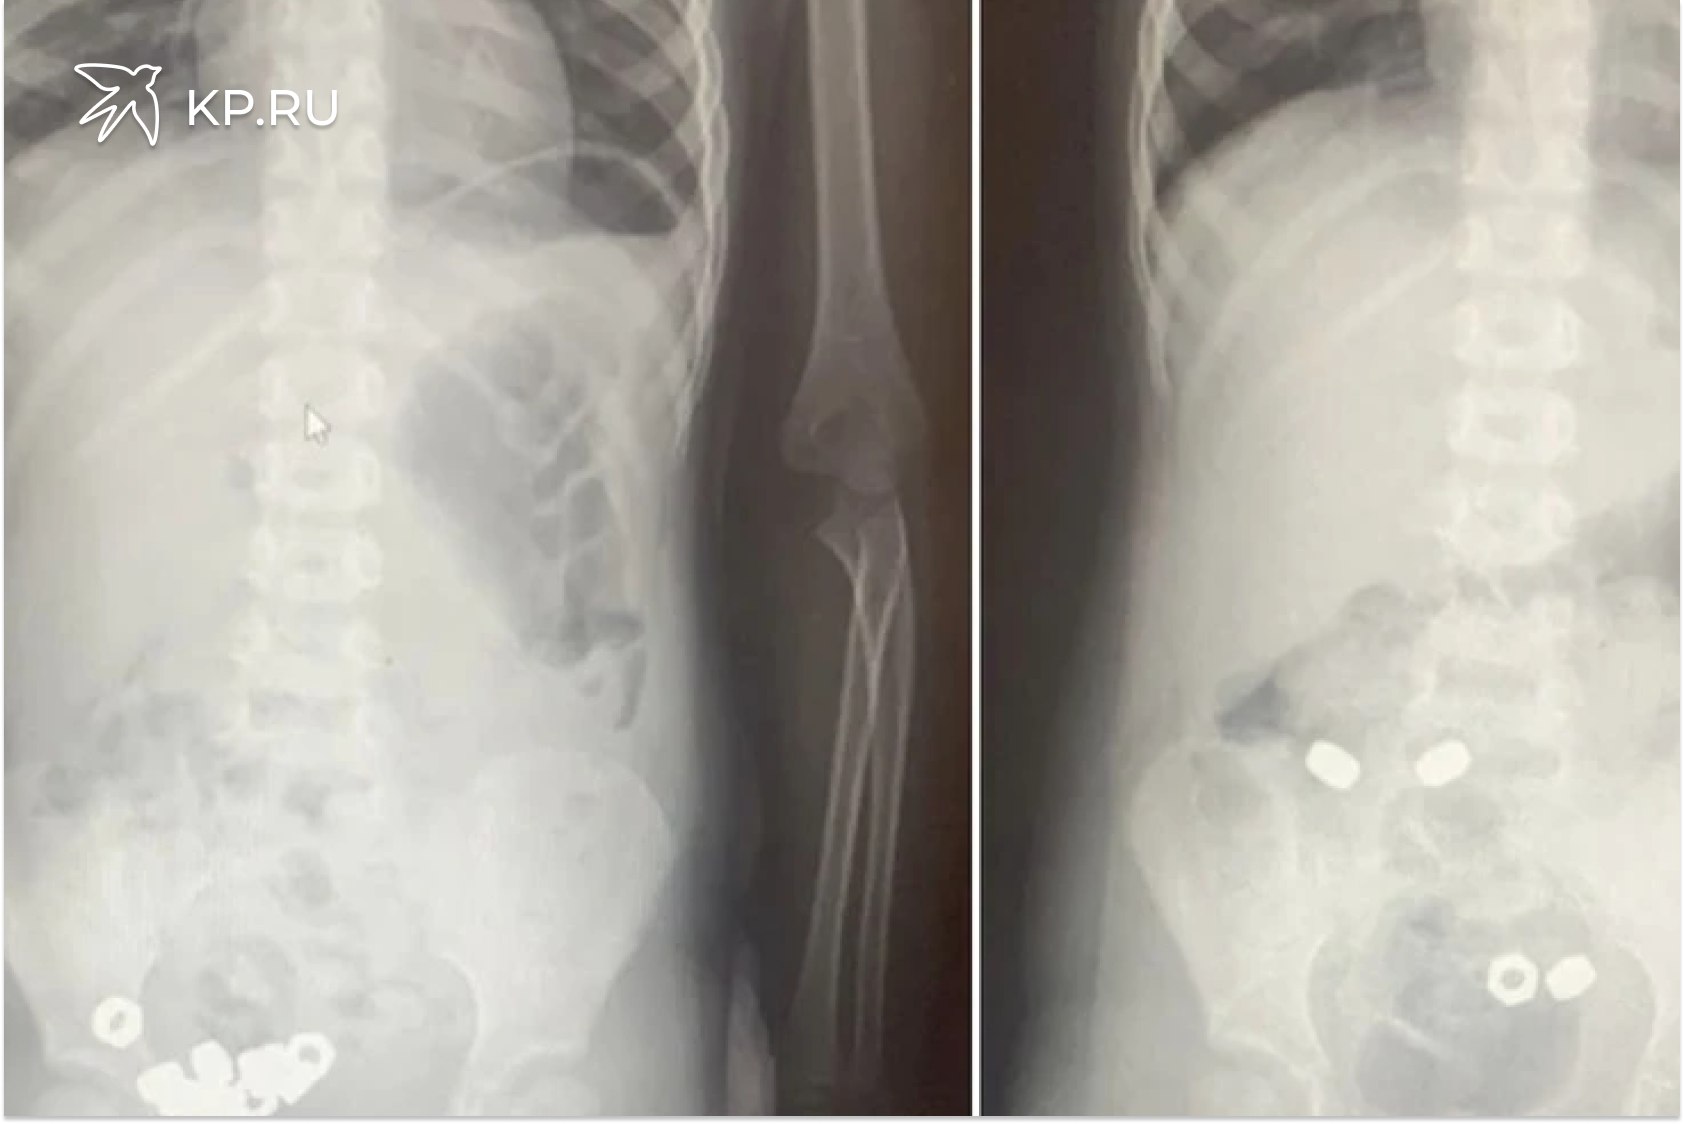

В Воронеже трехлетний малыш проглотил 16 гаек У 3 летнего ребенка воронежские врачи обнаружили в животе 16 гаек Малыша привели на прием в областную детскую больницу 2 родители предположили что мальчик проглотил инородные предметы Хотя никаких болезненных симптомов не испытывал Рентген брюшной полости действительно показал наличие множественных темных пятен в желудочно кишечном тракте ребенка Малыша госпитализировали чтобы исключить риск осложнений Инородные тела были не магнитные поэтому врачи выбрали консервативную тактику назначили диету покой контроль стула и рентгенографию в динамике К третьему дню все инородные тела успешно вышли естественным путем Оказалось что ребенок проглотил 16 гаек Малыша уже выписали сообщили в ОДКБ 2

В Воронеже трёхлетний малыш наелся гаек К счастью всё обошлось В детскую больницу 2 привезли трёхлетнего мальчика Родители заподозрили что он мог проглотить что то опасное Сам ребёнок вёл себя как обычно но взрослые решили перестраховаться И правильно сделали Врачи сделали рентген и ахнули в животе у малыша нашли целых 16 металлических гаек Его тут же оставили в больнице под присмотром Но резать не стали Доктора решили что раз это не магниты которые могут слипнуться внутри и повредить органы то можно попробовать обойтись без операции Мальчику прописали покой и специальную диету И этот план сработал За три дня все 16 гаек вышли из организма сами естественным путём После этого здорового и невредимого ребёнка выписали домой Врачи говорят что малышу очень повезло и ещё раз просят всех родителей пожалуйста убирайте подальше от детей любые мелкие предметы